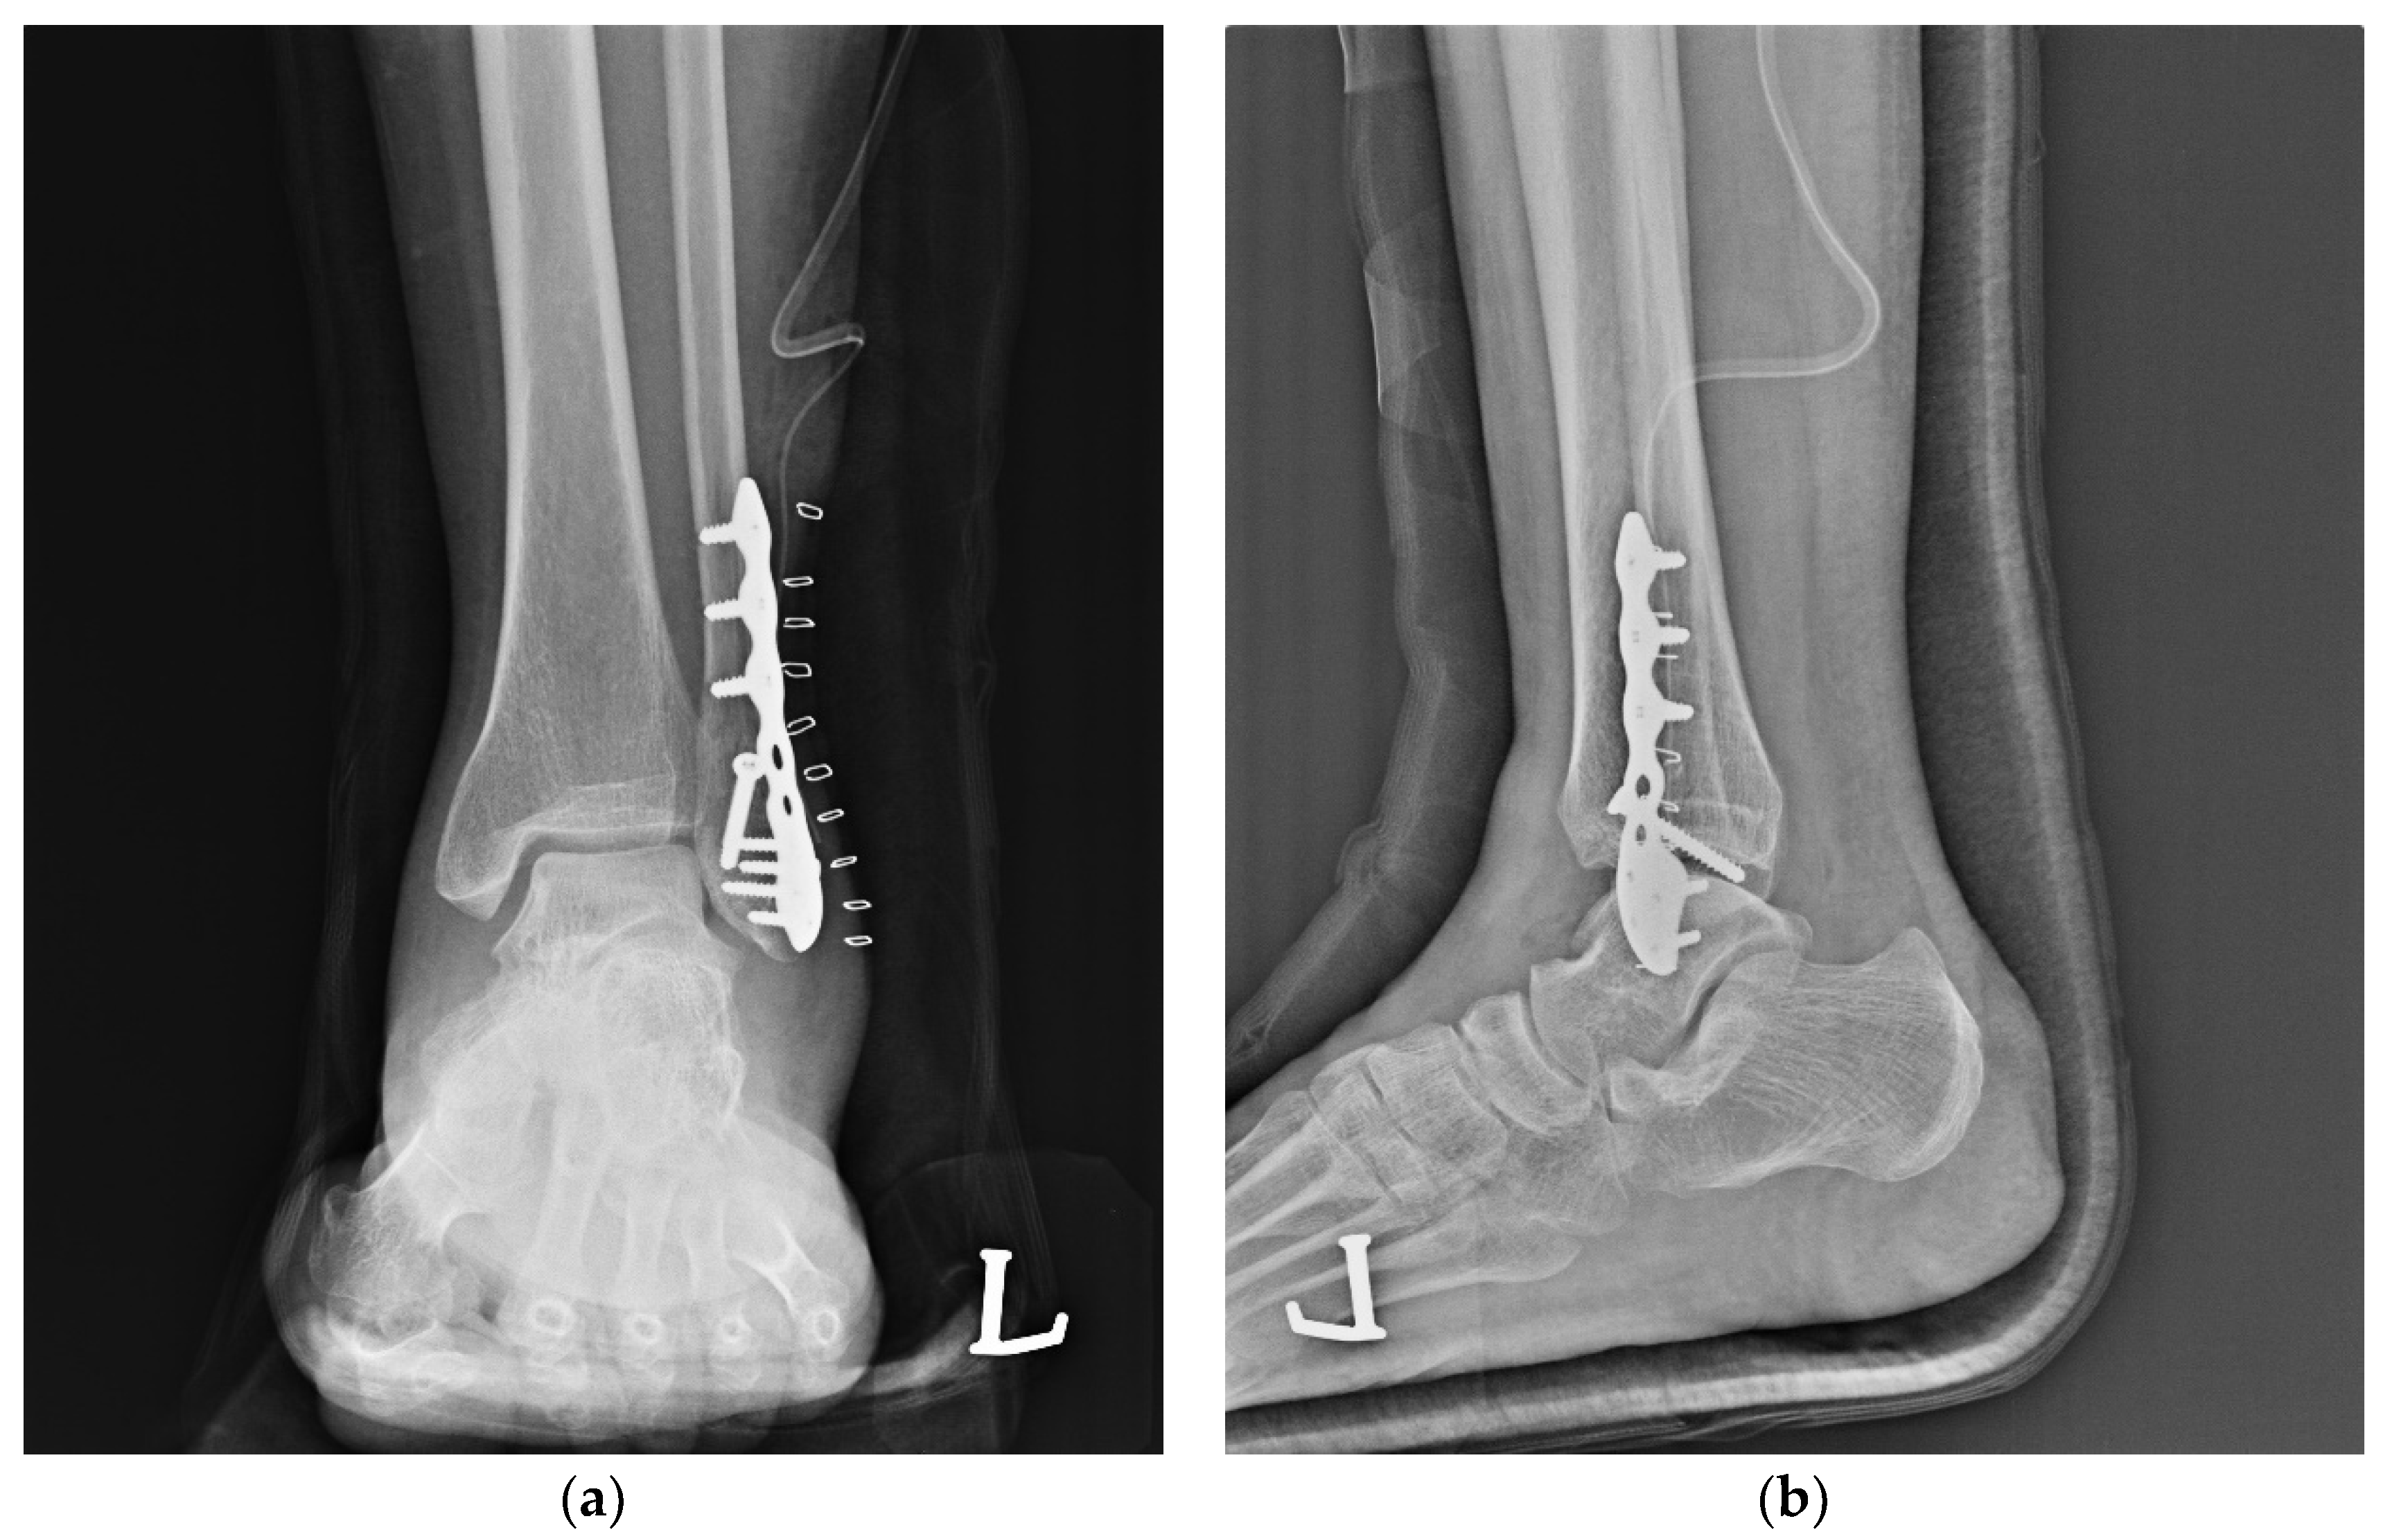

2.2. Surgical Technique